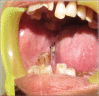

Salivary gland swellings can result from tumors, an inflammatory process or cysts. It can sometimes be difficult to establish; whether pathology arises from the salivary gland itself or adjacent structures. Neoplasms of the salivary glands account for less than 1% of all tumors, 3-5% of all head and neck tumors and benign pleomorphic adenoma (PA) of minor salivary glands arising de novo is very rare. PA is the most common tumor of the salivary gland. While the majority arises from the parotid gland, only a small percentage arises from the buccal minor salivary gland. A case of PA of minor salivary glands in the buccal mucosa in a 70-year-old female is discussed. It includes review of literature, clinical features, histopathology, radiological findings and treatment of the tumor; with emphasis on diagnosis.